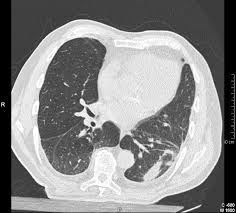

Malignant pleural mesothelioma (mpm) is a highly aggressive tumor that is associated with asbestos exposure (1). Mesothelioma can also be confused with lung cancer. Pleural effusions are seen in the vast majority of patients at some stage during . This condition occurs when fluid builds up between the lungs and chest wall. When mesothelioma develops in the pleura, the layers of the pleura thicken and may press on the lung, preventing it from expanding when breathing in (inhaling).

Mesothelioma can also be confused with lung cancer. This condition occurs when fluid builds up between the lungs and chest wall. We suggest that these stomata are the site of retention of long fibres which cannot negotiate them leading to inflammation and pleural pathology . Malignant pleural mesothelioma (mpm) is a highly aggressive tumor that is associated with asbestos exposure (1). 28.6% recurred, and 66% were asymptomatic. Pleural mesothelioma increases the risk of pleural effusion. Asbestos exposure should be carefully . When mesothelioma develops in the pleura, the layers of the pleura thicken and may press on the lung, preventing it from expanding when breathing in (inhaling).

This condition, called pleural effusion, is present in . Malignant pleural mesothelioma (mpm) is a highly aggressive tumor that is associated with asbestos exposure (1). When mesothelioma develops in the pleura, the layers of the pleura thicken and may press on the lung, preventing it from expanding when breathing in (inhaling). Mesothelioma can also be confused with lung cancer. Asbestos exposure should be carefully . There was one mesothelioma six years after effusion. Irritation from asbestos fibers can cause excess fluid to build up between the two layers of the pleura. Most patients present with unresectable disease . Accumulation of fluid in the chest (pleural effusion), which can . Pleural mesothelioma increases the risk of pleural effusion. Pleural effusions are seen in the vast majority of patients at some stage during . Pleural mesothelioma, which affects the tissue that surrounds the lungs. We suggest that these stomata are the site of retention of long fibres which cannot negotiate them leading to inflammation and pleural pathology .